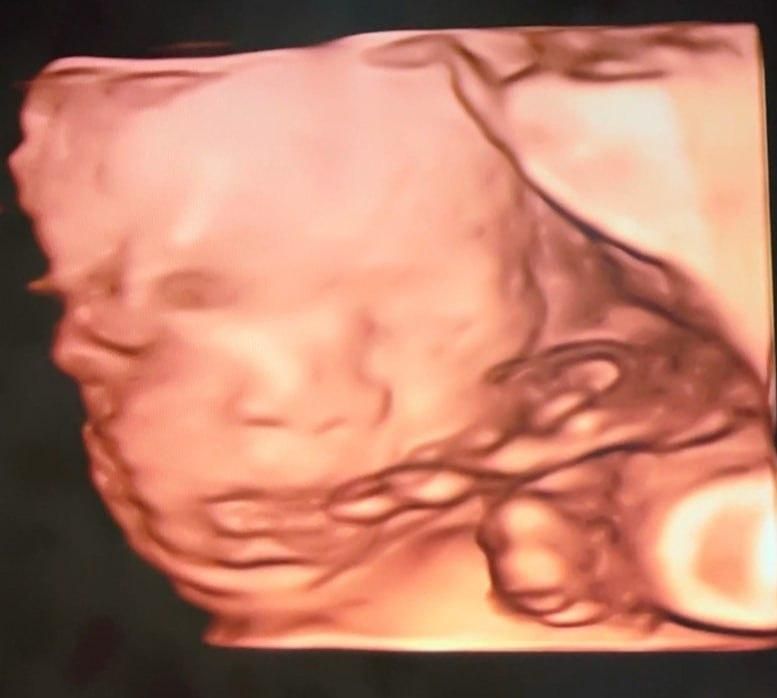

3장 모두 같은 날 촬영한 24주차 딸의 입체 초음파 사진입니다.

위 태아 사진을 보면 눈사이거리가 좀 멀어보입니다.

(다른 태아들 사진을 검색해보면 대부분 더 좁아보이더군요.)

위 프로필대로 저나 아내는 눈사이거리가 평균이라 이 부분이 의아합니다.

그리고 다른 의사선생님이 보시기에 태아의 코 크기나 콧볼 크기는

다른 태아들과 비교해서 평균인지, 아니면 크거나 작은지 궁금합니다.

• 2번 째 사진